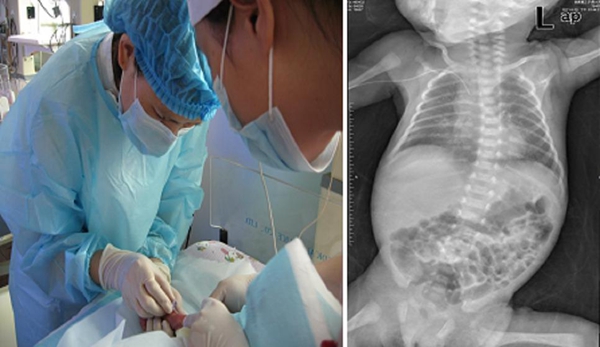

日前,我院新生儿科成功为一对低体重双胞胎早产危重患儿(体重分别为1.5kg、1.4kg)施行留置针替代导入鞘法成功置入PICC导管,解决了早产儿需要长期静脉输液和静脉营养治疗的护理难题,为挽救危重新生儿及低出生体重儿开辟了持续、有效的生命通道。目前患儿病情稳定,静脉营养持续下体重稳步增长。

据介绍,目前,PICC置管技术在医院成人患者中已经得到广泛应用,但对于早产儿,由于其技术要求高,操作过程复杂,置管难度较大。我院儿科成功开展此项技术,为本地区早产儿带来了福音,并进一步提高了早产儿的诊疗护理水平。